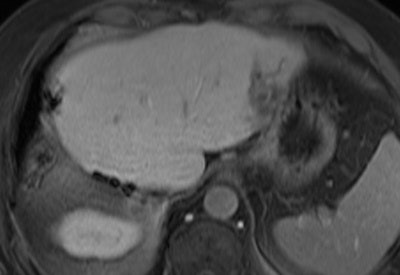

Above: MRI of an active liver metastasis near the gastric wall (parts of the liver had already been surgically removed two years previously). Below: Three IRE probes surround the tumor. Bottom: Signs of a tissue-sparing destruction of the liver metastasis in the CT review after the procedure.Images courtesy of Dr. Christian Stroszczynski, Regensburg University Hospital.

Electroporation is used at present to treat liver tumors, Stroszczynski noted. The liver is frequently affected both by primary tumors (hepatocelluar carcinoma) and metastases, and is well suited to local, minimally invasive therapies such as those used in interventional radiology for some years and with growing success.

"The liver is easily accessible with our working equipment, the probes introduced through the skin (percutaneously), and also the tissue is relatively robust and easily viewed anatomically," he explained.